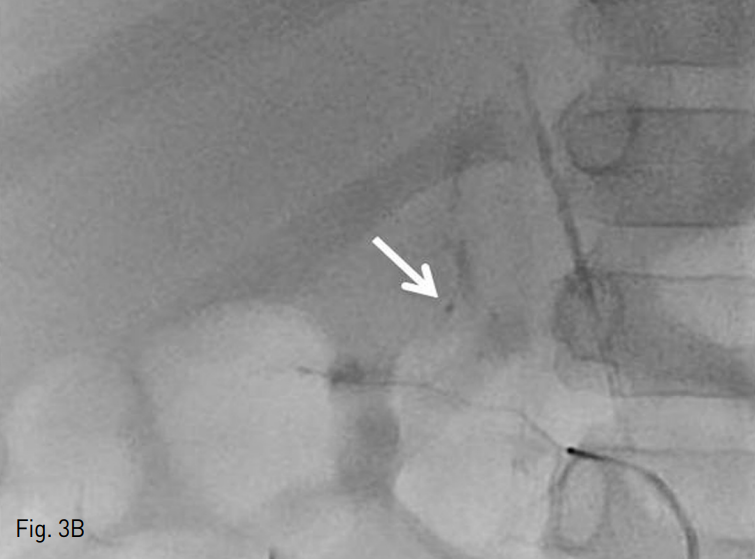

이후 4Fr cobra catheter를 통한 추적 오른쪽 아래가로막동맥조영술에서 상, 중 부신동맥에 대한 색전은 잘 확인되나, 하 부신동맥을 통한 혈류 흐름이 확인되었다 (Fig. 3A). 이에 하 부신동맥에 대한 보다 자세한 평가를 위해 microcatheter를 사용하여 하 부신동맥을 초 선택하였고, 선택적 조영술 상에서 오른쪽 부신의 하부 실질이 확인되나, 활동성 출혈이 있는지 여부는 확실히 배제할 수 없었다. 이에 Gelfoam (Alicon, Zhejiang, China)을 이용하여 색전을 시행하였다. 그러나 시술 과정 중 작은 가성동맥류가 확인되어 (Fig. 3B), NBCA와 Lipiodol 혼합물을 사용하여 추가 색전술을 시행하였다. 이후 추적 오른쪽 아래가로막동맥조영술에서 혈관 외 유출이 없음을 확인하고 시술을 종료하였다 (Fig. 4).

B. While taking embolization of right inferior adrenal artery, we found out the pseudoaneurysm (arrow) at the right inferior adrenal artery. So we took additional embolization about the pseudoaneurysm with mixture of Lipiodol and NBCA.